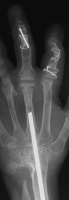

Clinical Example: Rheumatoid reconstruction with metacarpal head bone graft to recreate proximal phalanx dorsal cortex for silastic MCP arthroplasty

Rheumatoid arthritis commonly affects the hands in a variety of ways. Although more effective medications have lessened the number of patients requiring reconstruction for rheumatoid hand deformities, surgery is needed for some cases. This case demonstrates MCP arthroplasty using bone graft from the metacarpal head to recreate the dorsal cortex of the proximal phalanx lost from chronic subluxation.

Xrays show radiocarpal collapse, proximal migration of the proximal phalanges, flail PIP joints and loss of the proximal half of the dorsal cortex of the proximal phalanges.